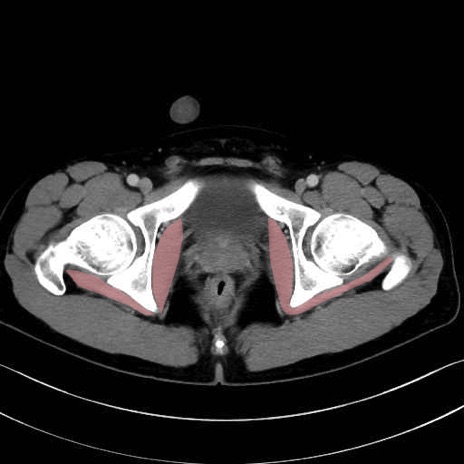

内閉鎖筋(obturator internus) のCT画像の解剖

内閉鎖筋 (Obturator internus)